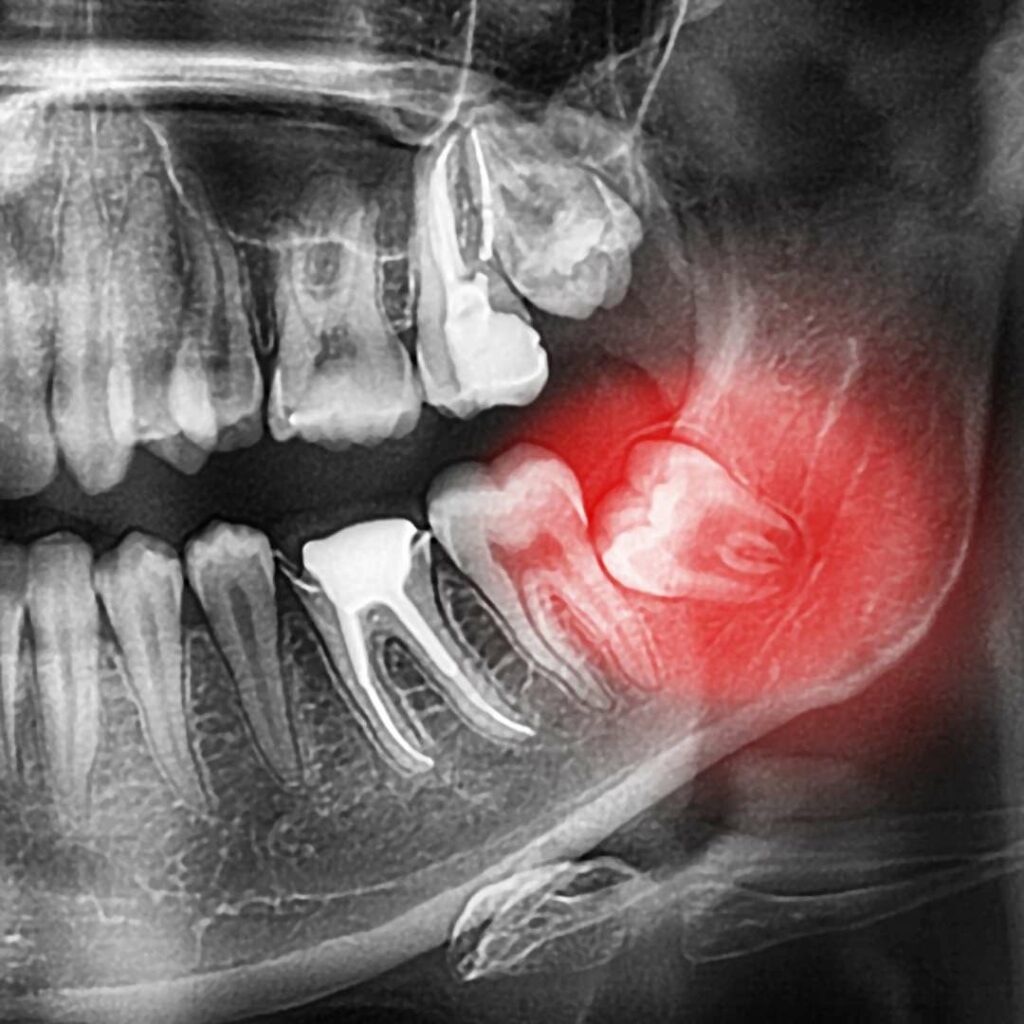

Our dentists believe that it’s always preferable to save a natural tooth, nonetheless there are some cases when it’s not possible. If you have a tooth that is too badly damaged as a result of decay, gum disease or injury, your dentist may recommend a tooth extraction. Additionally, wisdom teeth often need to be extracted to make room in your jaw or improve your dental health.

We’re equipped and ready to help you with any type of dental extraction. We offer both surgical and common extractions, including wisdom teeth extractions.